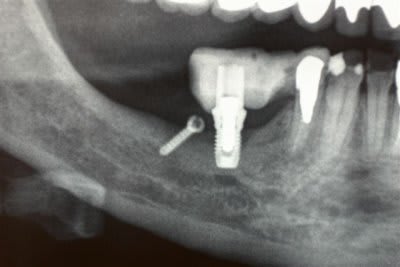

3 Radiographie Panoramique de la correction

5 Un bridge transitoire a été mis en place deux jours après la pose des implants

et roule mais pour la pérennité du cas une équilibration due l'ensemble de la bouche .....